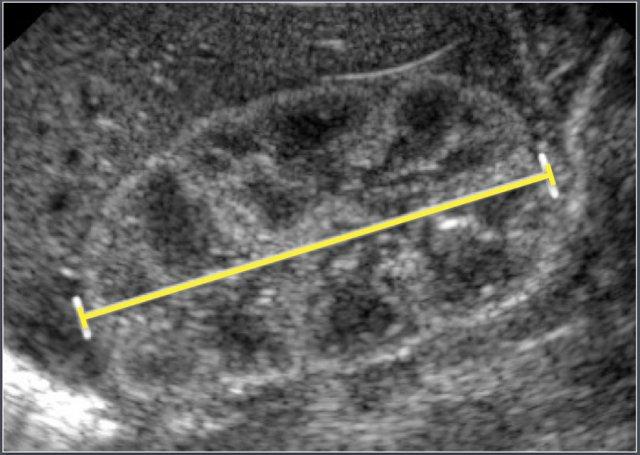

Đo chiều dài thận sơ sinh trên siêu âm.

Ở trẻ sơ sinh, nhu mô thận thường có độ hồi âm cao hơn nhu mô gan, đây là hình ảnh bình thường ở lứa tuổi này.